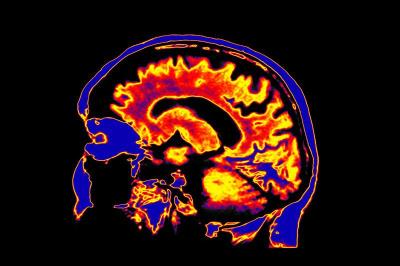

The application of single or multi-modality imaging for the spatio-temporal visualization of physiology and molecules including their function in biological and disease processes. Examples of the former may include analysis of receptors, metabolic changes, molecular motion, and blood flow. Example techniques include optical, nuclear medicine, MR, CT and ultrasound.